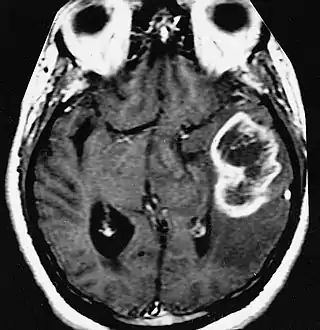

En las imágenes de TC y RM se muestra como una lesión heterogénea, de contorno irregular, que capta contraste en anillo y con un área central necrótica.

Diagnóstico por imagen y glioblastoma

La TC muestra una lesión de morfología irregular, predominantemente hipodensa y fuertemente dishomogénea, debido a la presencia de grandes áreas necróticas de más clara hipodensidad y de áreas sólidas hiperdensas. Estas últimas son la expresión de un rápido crecimiento y por lo tanto de una elevada malignidad. Son frecuentes las zonas hemorrágicas, que van desde pequeños focos a grandes áreas hemáticas que pueden cubrir toda la lesión. Es característica la morfología en "mariposa" si el tumor se asienta en ambos hemisferios a través del cuerpo calloso.

Tras la aplicación de contraste aparecen gruesos anillos alrededor de las áreas necróticas. En la RM, la parte sólida aparece hipointensa en T1 e hiperintensa en T2 con zonas de señal más elevada en las partes de mayor celularidad. Las áreas necróticas, hiperintensas en T2, pueden presentarse hipo-, iso- o hiperintensas en T1 en función del contenido proteico o de productos de la degradación de la hemoglobina. El realce tras el contraste suele ser intenso e irregular en la periferia del tumor e identifica sobre todo la componente celular "proliferativa" de la neoplasia. Son comunes las áreas puntiformes y serpiginosas de ausencia de señal de flujo, asociadas a la presencia de una neovascularización rica. Estos vasos de neoformación patológica carecen de barrera hematoencefálica, lo que explica tanto la abundante impregnación como el edema vasogénico perilesional (véase la sección anterior), debido al paso de líquido al medio extracelular.[71][72]